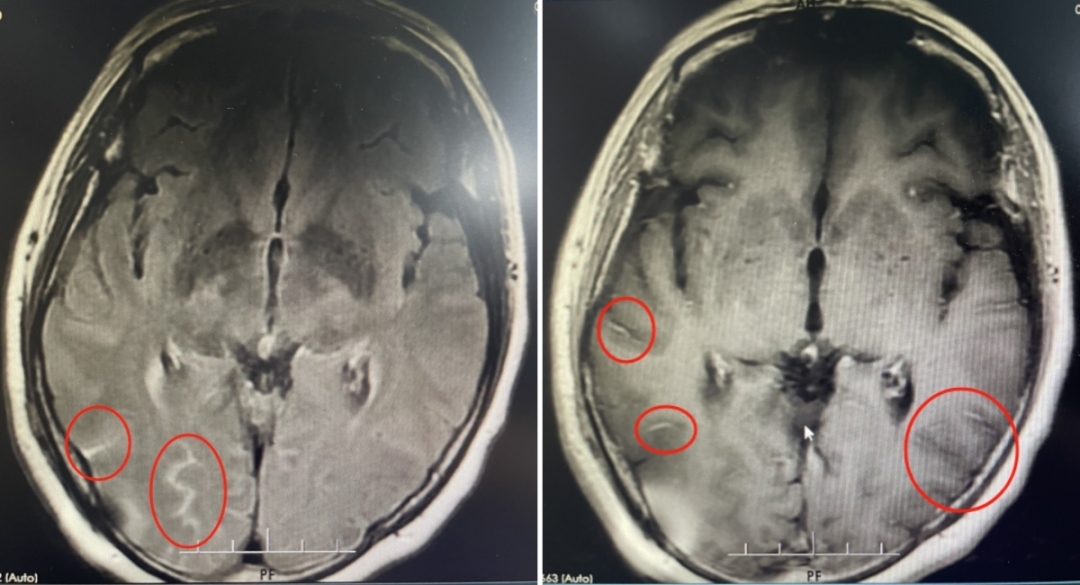

该院神经内一科副主任匡祖颖接诊后,怀疑患者是脑膜炎的可能性较大。最终通过腰穿检查在患者的脑脊液涂片中发现了隐球菌,从而确诊为隐球菌脑膜炎。

尽管立即采用了抗真菌等对因治疗,但患者在住院期间还是出现了左眼视力下降,连光感都丧失了。复查腰椎穿刺发现脑脊液压力增高,提示颅高压。为避免长期高颅压导致头痛及颅神经损伤,匡祖颖安排患者转入神经外科行脑室腹腔分流术。